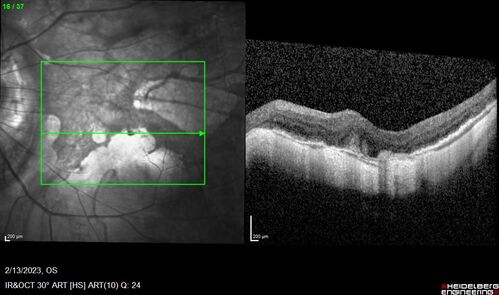

Myopic CNVM Left Eye

80 year old female. VA dropped to 20/125 but improved back up to 20/50 with Vabysmo